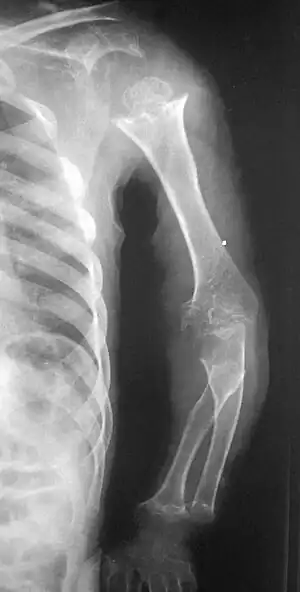

| Pseudoachondroplasia. Shoulders and Humeri. Note the dysplastic proximal humeral epiphyses, metaphyseal broadening, irregularity and metaphyseal line of ossification. These changes are collectively known as "rachitic-like changes". Lesions are bilateral and symmetrical. | |

- Together with rhizomelic limb shortening, the presence of epiphyseal-metaphyseal changes of the long bones is a distinctive radiologic feature of pseudoachondroplasia.

- Dysplastic/hypoplastic epiphyses especially of shoulders and around the knees.

- Metaphyseal broadening, irregularity and metaphyseal line of ossification. These abnormalities that are typically encountered in proximal humerus and around the knees are collectively known as “rachitic-like changes”.

- Radiographic lesions of the appendicular skeleton are typically bilateral and symmetric.